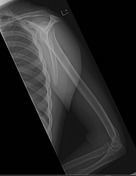

| AP Humerus | humeral epicodyles not in profile radial head, neck and tuberosity to not superimpose ulna arm is externally rotated (greater tubercle in profile) |

| Lateral Humerus | over rotation places the humeral head within the field of the chest |

| Lateral Humerus | epicondyles are not perpendicular humerus is internally rotated (lesser tubercle is in profile medially) overrotation |

| AP Humerus | ANATOMY: entire humerus: shoulder -> elbow CRITERIA: greater tubercle in profile - hand externally rotated humeral epicondyles are parallel to IR POSITIONING: CR perpendicular @ midhumerus |

| Lateral Humerus | ANATOMY: entire humerus: shoulder -> elbow CRITERIA: lesser tubercle in profile - arm internally rotated epicondyles superimposed POSITIONING: pt rotated 15-20 degrees from PA to get arm lateral and away from chest - flex elbow 90 degrees CR perpendicular @ midhumerus |